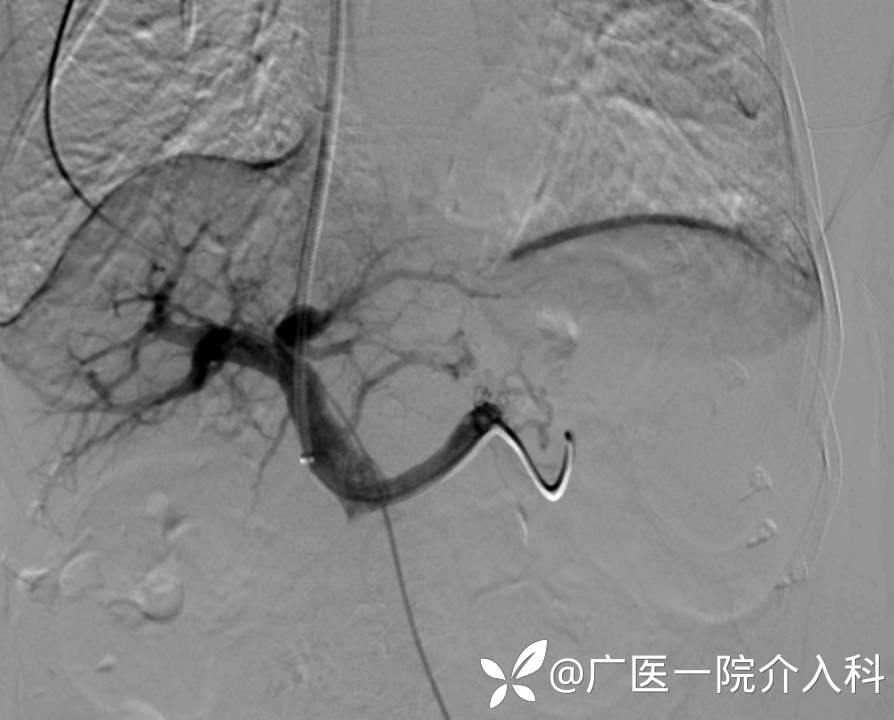

治疗方案:经熊斌教授指导,肝肠外科郭健副主任医师为患者进行经颈动脉内肝门体静脉分流术(TIPS)。

经颈静脉肝内门体支架分流术(TIPS)